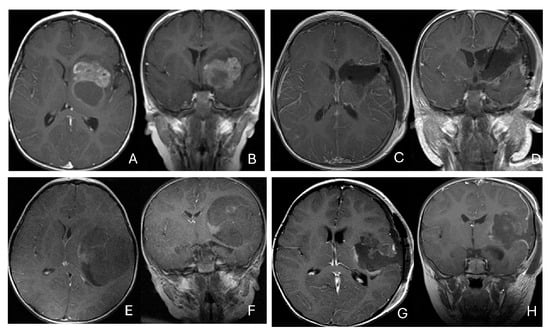

Objectives: Atypical teratoid/rhabdoid tumors (ATRTs) are rare, malignant central nervous system (CNS) neoplasms that predominantly affect infants and young children. While ATRT arises throughout the CNS, its extracranial counterpart, malignant rhabdoid tumor, occurs in other organs. A single-institutional cohort is reviewed to map

Objectives: Atypical teratoid/rhabdoid tumors (ATRTs) are rare, malignant central nervous system (CNS) neoplasms that predominantly affect infants and young children. While ATRT arises throughout the CNS, its extracranial counterpart, malignant rhabdoid tumor, occurs in other organs. A single-institutional cohort is reviewed to map anatomic distribution of pediatric ATRTs and to integrate a literature review to contextualize ATRT histogenesis from anatomical and embryological perspectives. Methods: A retrospective review was conducted on a cohort of 50 pediatric patients with ATRT treated over 20 years. Demographic, surgical, and neuroimaging data were correlated to define tumor location, extent, and compartmental involvement. A focused literature review synthesized molecular subclassifications and proposed cells of origin/cytogenesis. Results: Of the 50 ATRTs, 18 (36%) were infratentorial, 15 (30%) supratentorial, 11 (22%) in the pineal region, and 6 (12%) in the spinal compartment. Among infratentorial tumors, 10 were centered in the fourth ventricle, with or without extension into the cerebellopontine angle (CPA) cistern; the remainder arose in the CPA. Among ATRTs of the cerebral hemispheres, 3 showed bi-hemispheric involvement crossing the falx cerebri. ATRTs of the pineal region predominantly originated from the superior medullary velum. These topographic data were corelated with embryological and molecular information available in the literature. Conclusions: ATRTs arise across diverse neuroanatomical compartments—including intraparenchymal, intraventricular, extra-axial, and extradural sites—underscoring biological heterogeneity. Inactivation of SMARCB1 is the defining molecular event and principal oncogenic driver, although the upstream mechanisms precipitating these alterations remain incompletely resolved. Molecular subgroups—ATRT-TYR, ATRT-SHH, and ATRT-MYC—display distinct age distributions and anatomic predilections, implicating developmental context in tumor initiation. The characteristic cellular admixture of rhabdoid cells with mesenchymal and/or epithelial differentiation, together with intra- and extra-axial and occasional extradural presentations, supports a model in which at least a subset of ATRTs may originate from neural crest-derived lineages, despite little or no neural crest contribution to brain parenchyma development. Neural plate border progenitors with bipotent features represent a plausible intraparenchymal cell of origin. Definitive resolution of these origins and the mechanisms of SMARCB1 disruption will require integrated approaches. Further investigations are warranted to clarify these mechanisms.